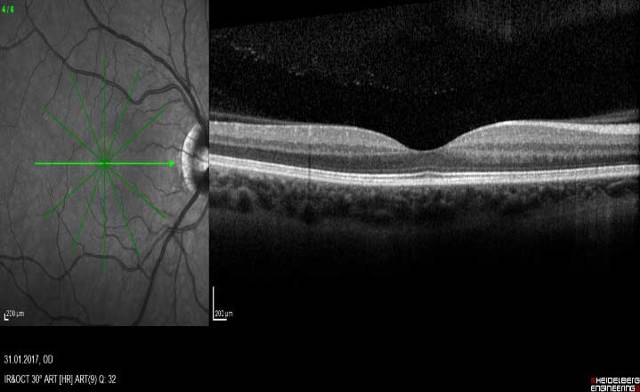

Диагностика зрения: Когерентная томография сетчатки